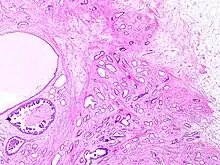

Tubular carcinoma is a subtype of invasive ductal carcinoma of the breast.[2][3] More rarely, tubular carcinomas may arise in the pancreas[4] or kidney.[5] Most tubular carcinomas begin in the milk duct of the breast and spread to healthy tissue around it.[6][7]

Although tubular carcinoma has been considered a special-type tumor,[lower-alpha 1] recent trend has been to classify it as a low-grade, invasive NOS carcinoma because there is a continuous spectrum from pure tubular carcinomas to mixed NOS[lower-alpha 2] carcinomas with tubular features, depending on the percentage of the lesion that displays tubular features.[10]: 647

Tubular carcinomas are generally around 1 cm. or smaller, and are made up of tubules. They are usually low-grade.[2] Elastosis has been noted as common but is not present in all cases.[11]

A highly differentiated invasive carcinoma that forms well-defined tubules (containing epithelium, but no myoepithelium) and that have abundant desmoplastic fibrous stromal reaction between the tubules.